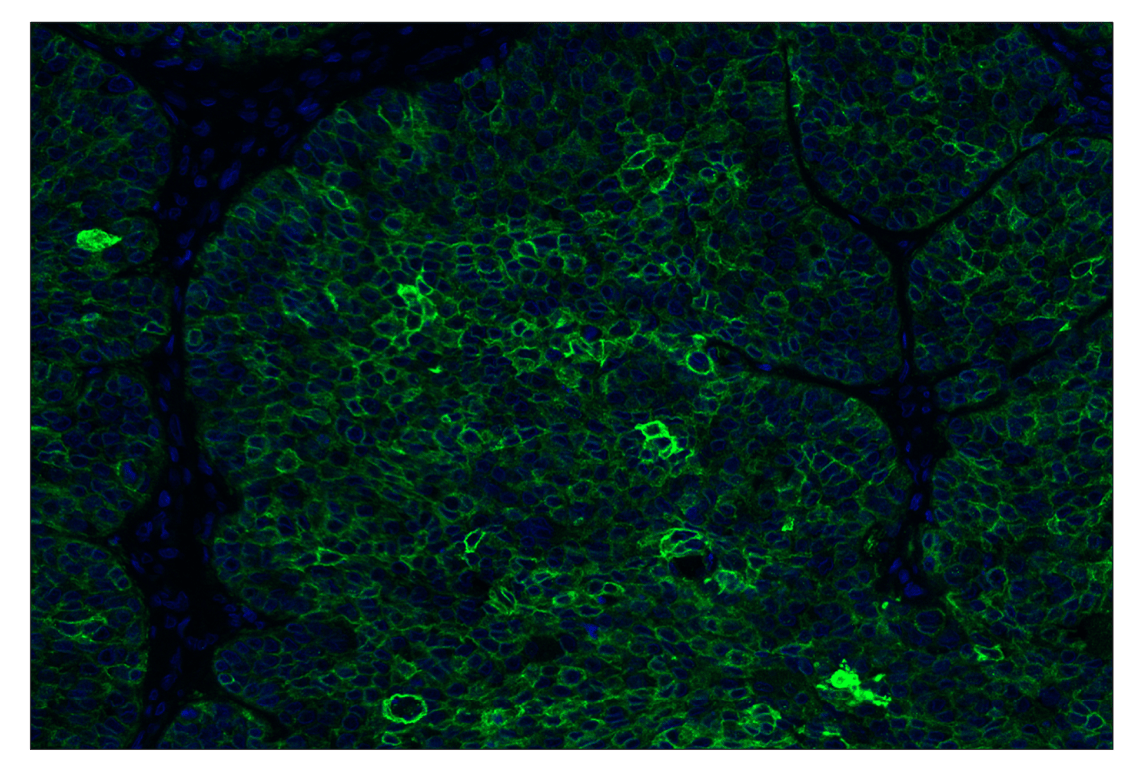

SignalStar™ multiplex immunohistochemical analysis of paraffin-embedded human squamous cell lung carcinoma using TACSTD2/TROP2 (F4W4J) & CO-0150-488 SignalStar™ Oligo-Antibody Pair #76304 (green) and DAPI #4083 (blue). All fluorophores have been assigned a pseudocolor, as indicated.

Immunohistochemistry Image 1: TACSTD2/TROP2 (F4W4J) & CO-0150-488 SignalStar<sup>™</sup> Oligo-Antibody Pair